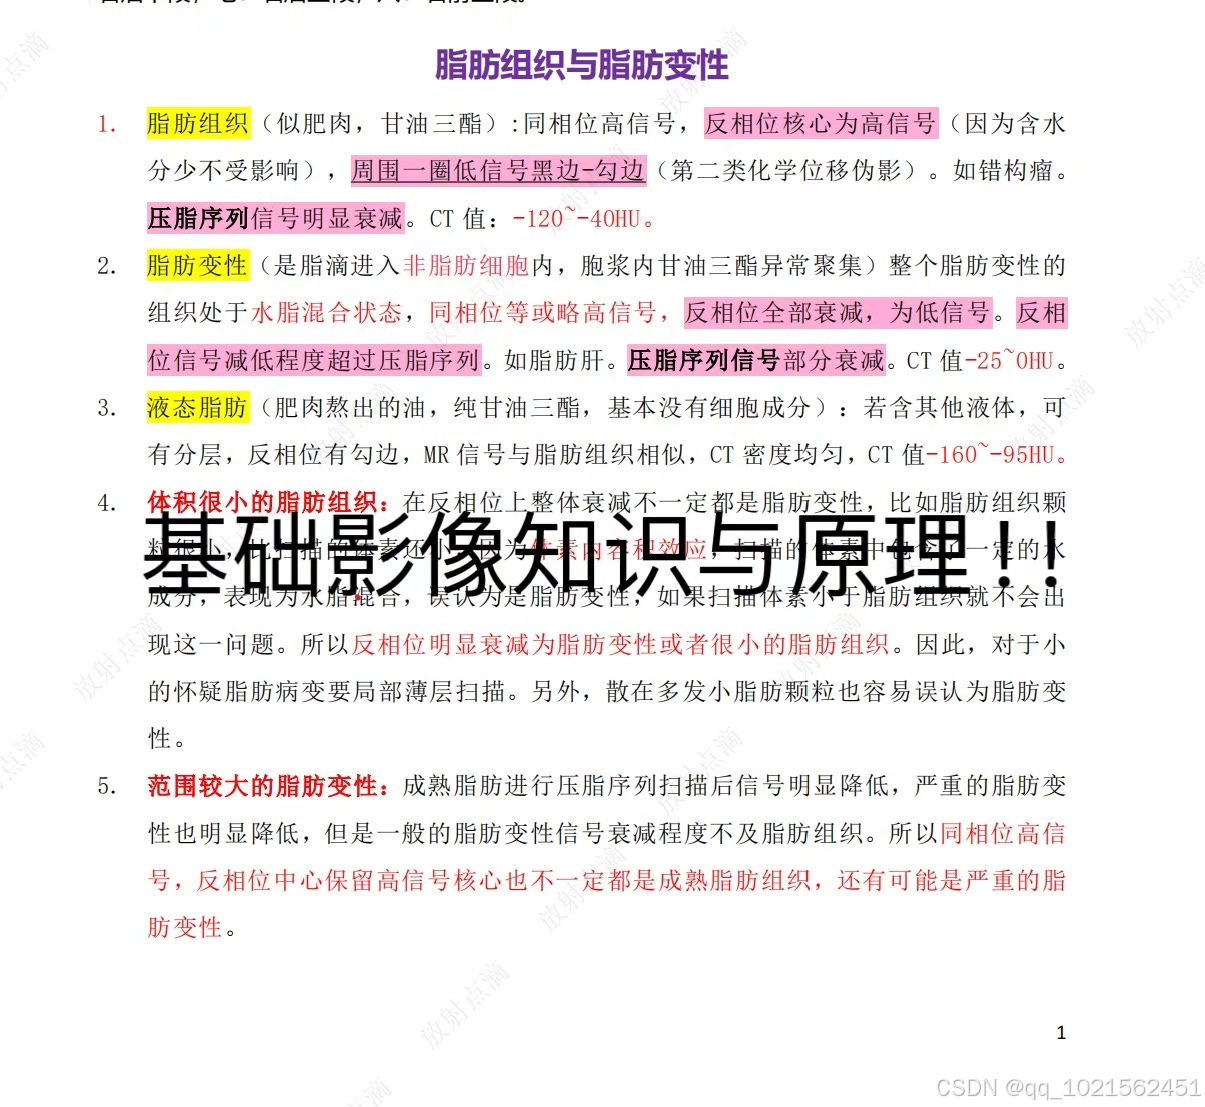

规培结业考试已通过,现分享自己花了大量时间和精力根据考点做的重点笔记,里面包含实际病例影像图片帮助记忆,横向和纵向鉴别诊断表格等,适合看不下去教材,没时间梳理和总结重点的朋友。

笔记来源:最初是为了研究生复试,收集了各个院校的笔试大题和面试专业题题干,然后根据教材的知识点,辅以各种其他书籍、专业公众号整理的答案,这里面不是单纯知识点的罗列,而是结合了实际考题进行了有逻辑的梳理,里面有很多鉴别诊断的表格,还有思维导图。最后背了自己整理的资料,考研面试成绩第一。后面在规培的过程中根据规培大纲和日常写报告的经验,又如法炮制,进一步完善了这份笔记,在规培结业考试的时候就直接省去了看教材这个过程,为我大大提升了效率,缩短了复习时间!!!!